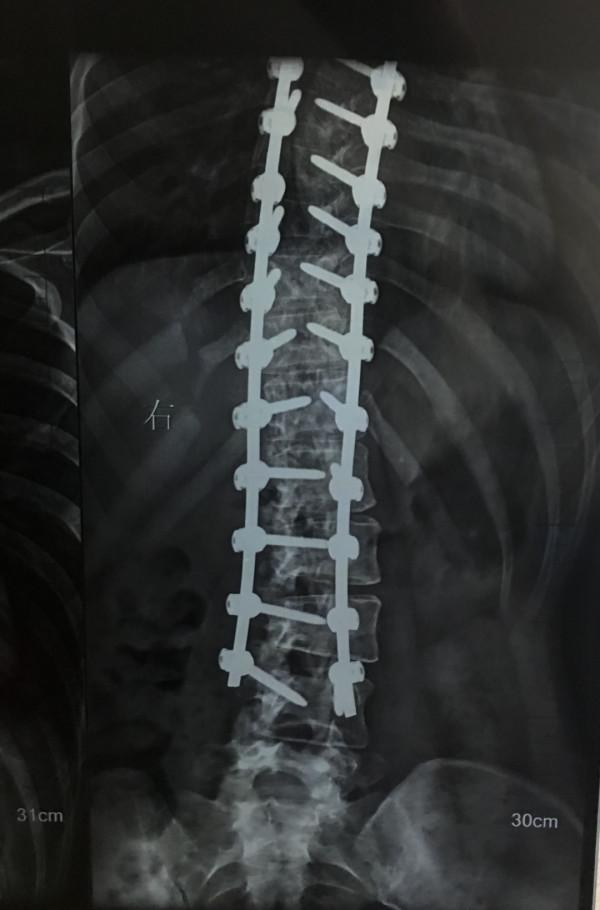

我知道我將被翻轉過來,光溜溜地趴在一大塊墊子上擺成小豬的姿勢,醫生會把我的背整個劃開,分開面板、脂肪和肌肉,在每節脊椎鑽孔、打入鈦合金鋼釘(國產),用兩根長長的鋼棒將它們連線起來,再一點點掰直,直到我的神經無法再承受拉長和移位。

手術後脊柱X線片 | 作者供圖

從胸椎第二節到腰椎第三節都打上了釘子,我戲稱自己是鈦合金鋼鐵俠,幸好每次安檢都順利透過。